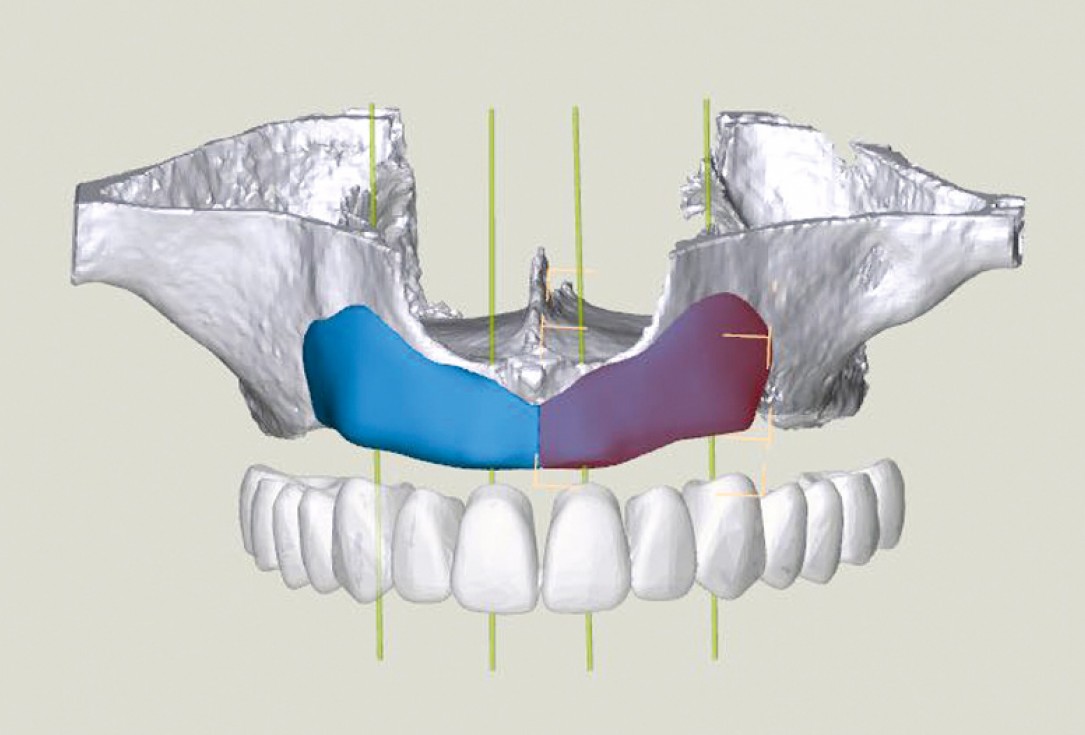

5/23 - 3D-Reconstruction of the maxilla including two maxgraft® bonebuilder blocks

Full arch reconstruction of the maxilla with maxgraft® bonebuilder - Dr. M. Erbshäuser